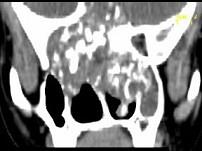

男,26岁,进行性鼻腔阻塞、流涕来院就诊,近两年持续性头痛、头晕,如图所示筛窦区占位灶应诊断为 ( )